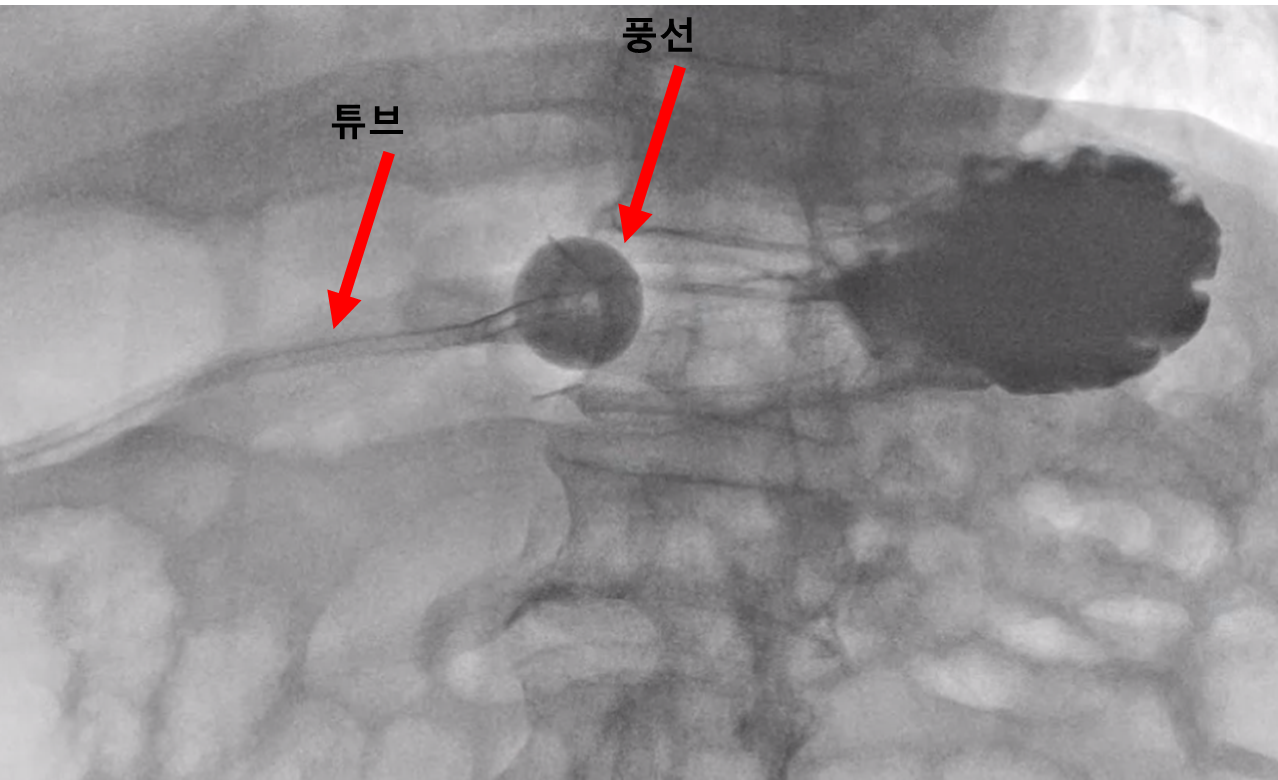

그 다음은 확장기구로 튜브가 들어갈 길을 넓히고

마지막으로 튜브를 넣고 튜브 끝 부분에 있는 풍선을 확장시켜 튜브가 빠지지 않게 고정한답니다.